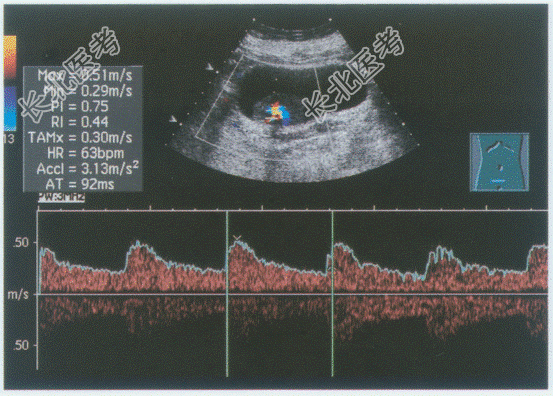

超声综合描述: 膀胱横切7:00~8: 00可见3.9cm×2.0cm中等回声,向膀胱内突起, 边界清晰,基底较宽, 内回声不均,CDFI: 内可见丰富动静脉血流信号,PW: 以动脉频谱为主。见下图及彩图。